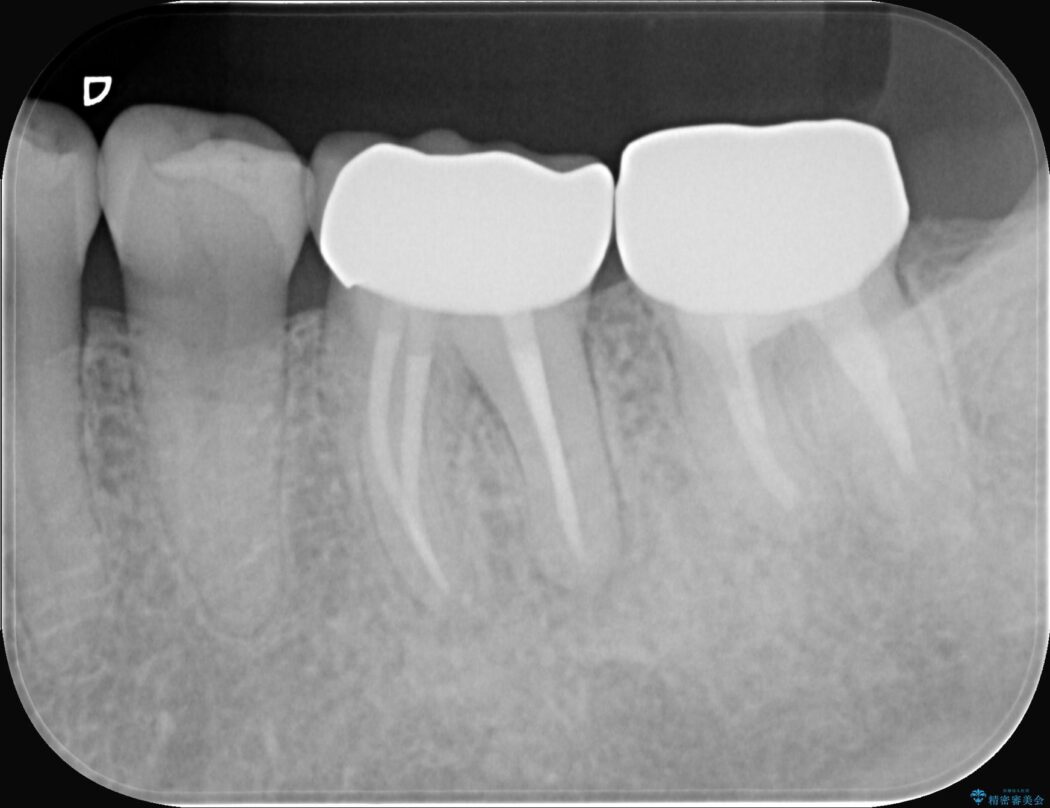

今回の治療は、特に難易度の高い石灰化した根管が対象でした。

まず、治療中の細菌感染を防ぐためにラバーダムを使用。次に、歯科用顕微鏡で治療部位を何十倍にも拡大しながら、狭窄した根管の入り口を探し、慎重に拡大・清掃を行いました。顕微鏡を用いることで、肉眼では不可能だった根管内部の細かい構造を確認しながら、感染源を徹底的に除去することができました。これにより、難症例の奥歯でも再発リスクを抑えた適切な処置を行うことができ、治療後に痛みは解消。大切な歯を長期間にわたり保存することができました。